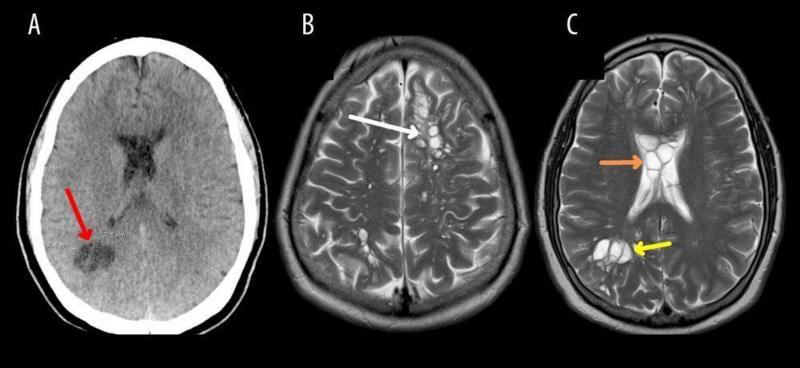

Bajo ese contexto, y al no entender por qué le dolía tanto la cabeza, los médicos decidieron realizarle varias tomografías, en las que se veían varios quistes en el cerebro. Sin embargo, con estudios posteriores, comprobaron que en verdad tenía larvas, las cuales causan una infección llamada neurocisticercosis.

Paciente tenía larvas en su cerebro